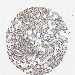

CANCER BREAST CANCER Show tissue menu

BRCA TCGA BRCA VALIDATION PROTEIN EXPRESSION